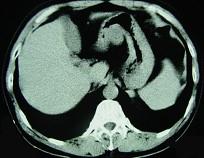

问题 男,52岁,中上腹痛,影像检查如图,最可能的诊断是 ( )

选项 A.慢性肥厚性胃炎 B.胃癌 C.胃溃疡 D.胃平滑肌瘤 E.胃平滑肌肉瘤

答案 D